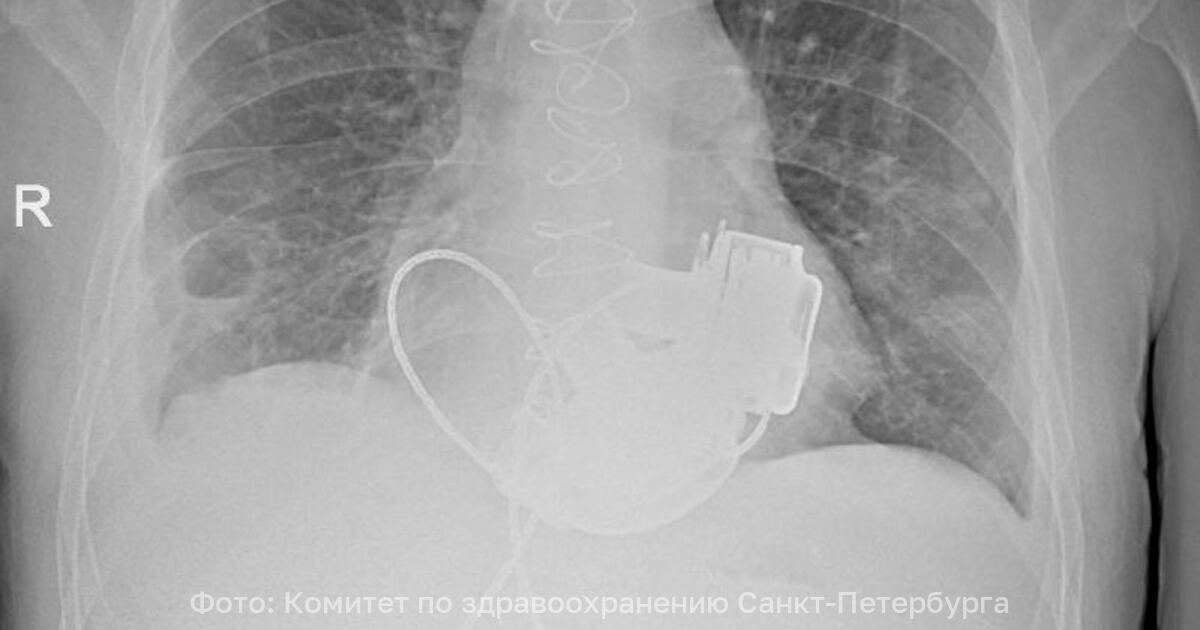

Пульса нет вообще, а вместо сердца — два пламенных мотора: в России впервые пациенту имплантировали оба желудочка - Новости Калининграда | Фото: Комитет по здравоохранению Санкт-Петербурга

Фото: Комитет по здравоохранению Санкт-Петербурга

В Санкт-Петербурге врачи готовят к выписке пациента, который теперь живёт без пульса. В конце ноября 2025 года 36-летнему мужчине имплантировали одновременно левый и правый искусственные желудочки сердца. Об этом рассказали в городском комитете по здравоохранению.

По словам главного врача Мариинской больницы Игоря Реутского, когда Антон поступил в стационар, показатели работы сердца были такими, будто человек уже не жив, а мёртв. При этом из-за сопутствующих осложнений трансплантация сердца была невозможна.

«Операция продолжалась около 4 часов. Для наших специалистов самым сложным было синхронизировать работу двух искусственных желудочков сердца, но с этой задачей мы успешно справились. Это доказывает высокий уровень развития кардиохирургии в нашем городе». — отметил главный внештатный специалист по сердечно-сосудистой хирургии Санкт-Петербурга Геннадий Хубулава.

Врачи надеются теперь вновь встретиться с Антоном, так как имплантация искусственных желудочков — «мостик» к трансплантации сердца, которую пациент теперь сможет дождаться.